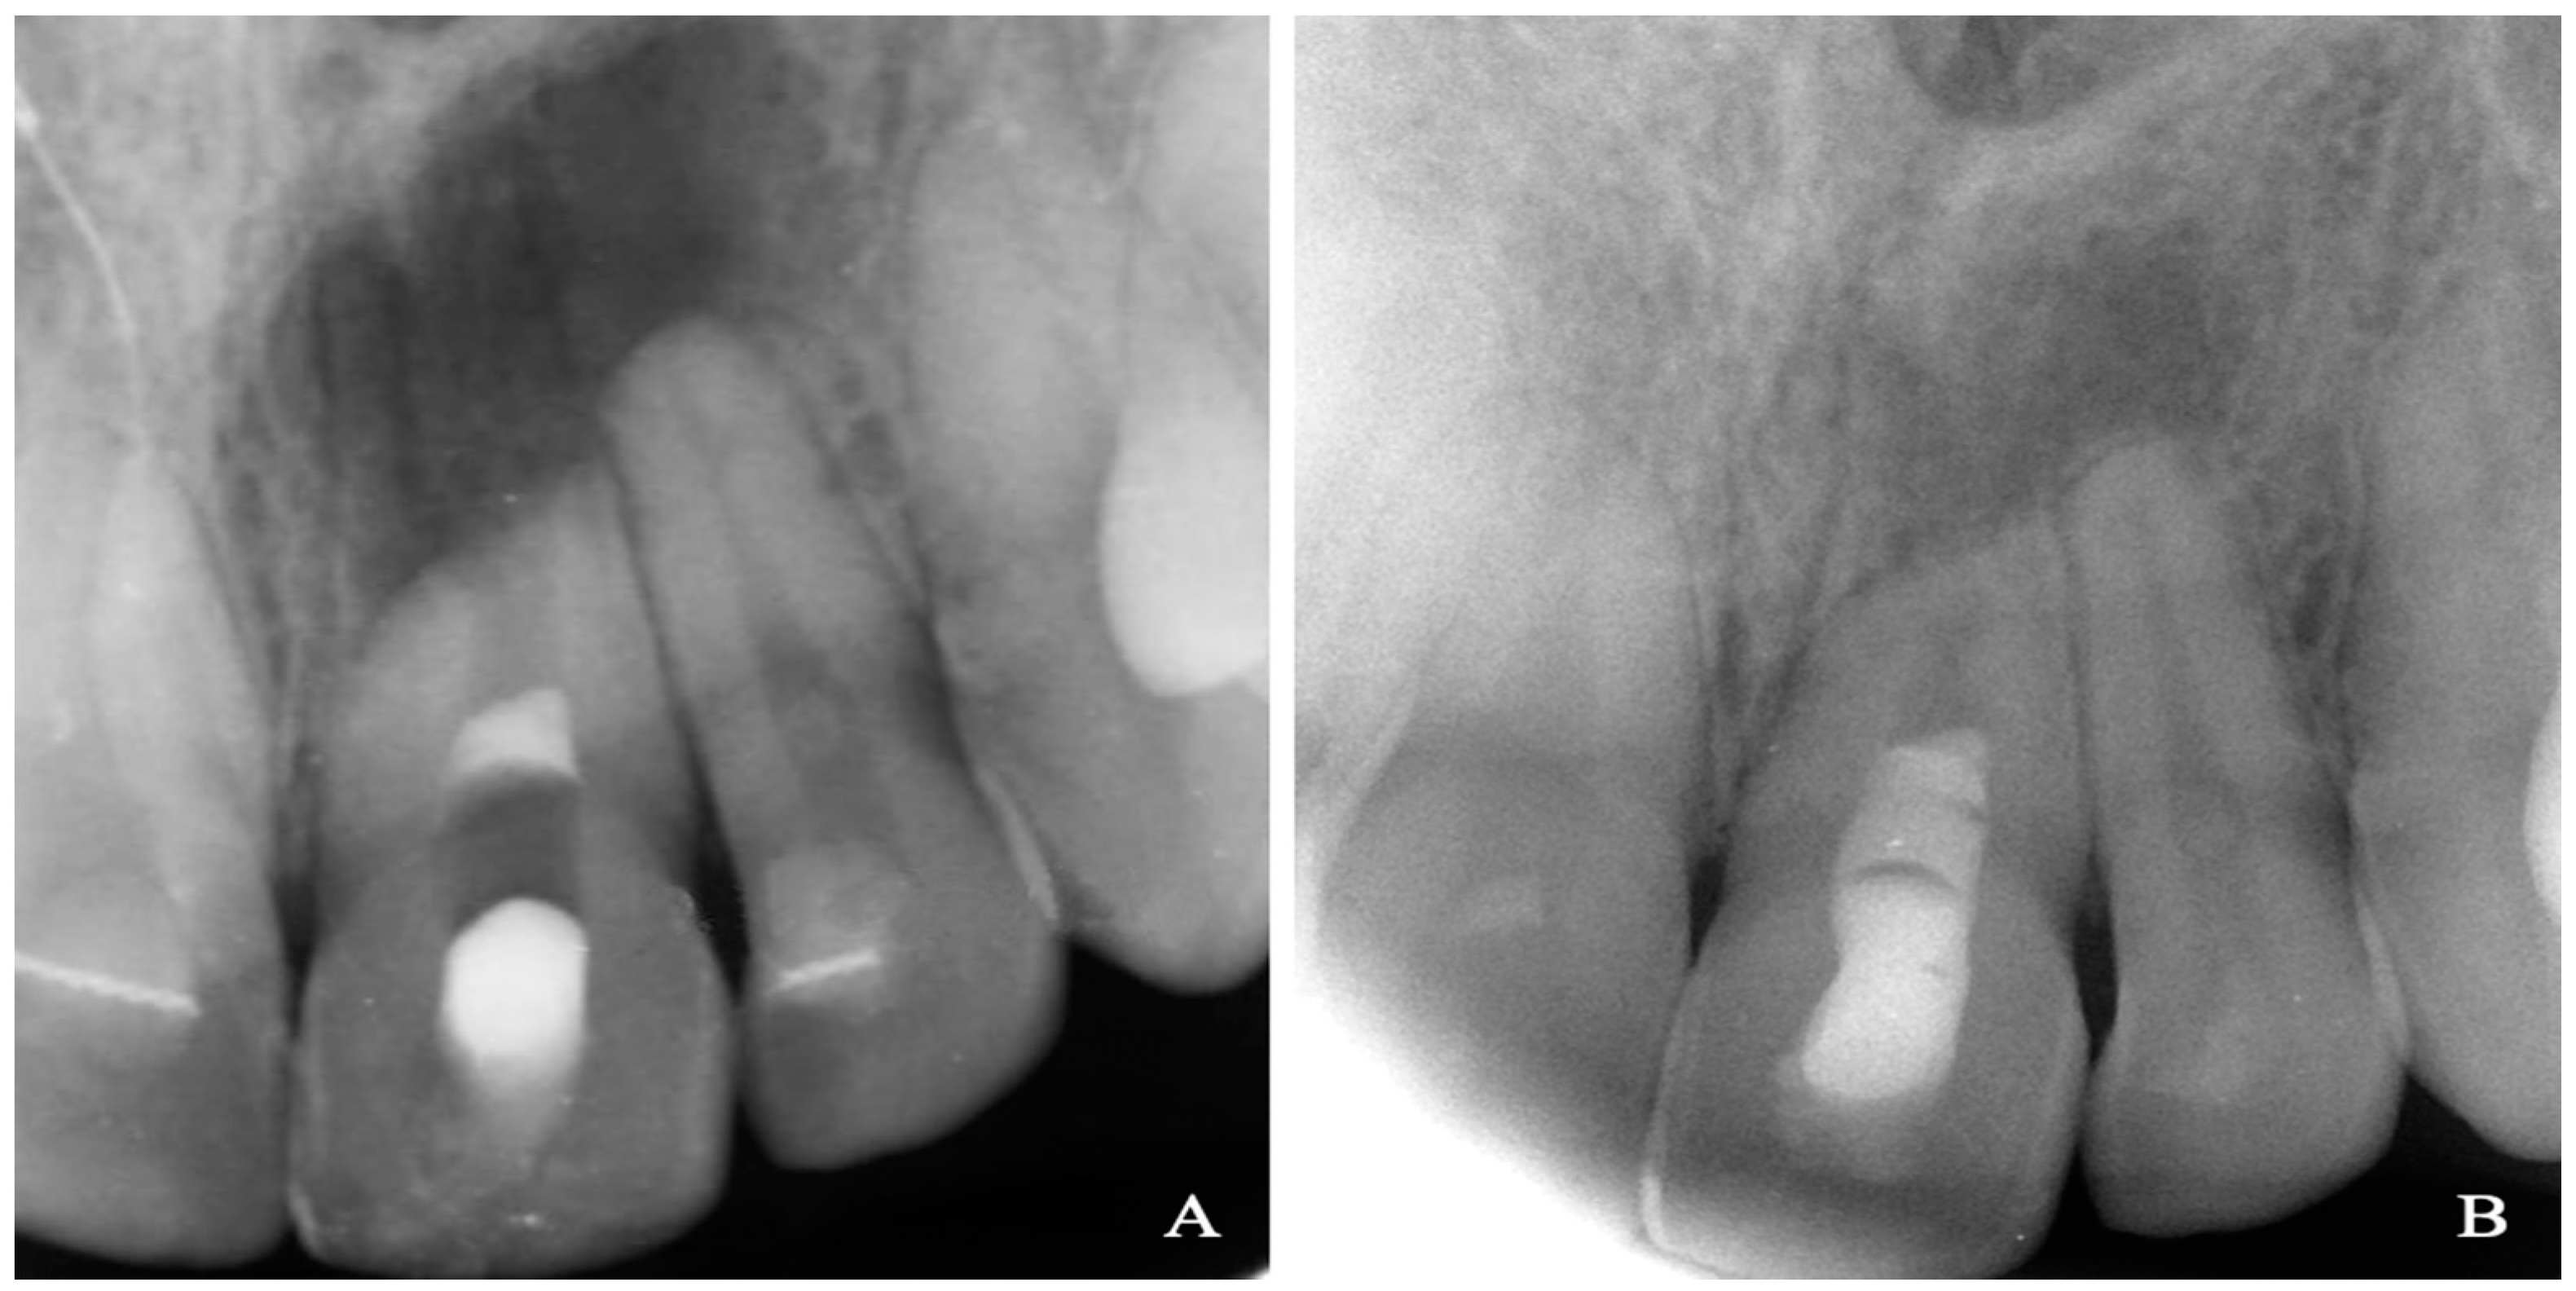

Although a closed apex is found in most of the adult teeth, it is possible to find immature teeth that physiologically should have already completed their root development, mainly due to a dental trauma, caries, or developmental anomaly, which led to the necrosis of the dental organ [24]. In Figure 1 is an adult patient’s immature central incisor, necrotic due to a dental trauma. Because of the age of the patient, in these cases, some conditions must be considered. 1. Reduced revascularization potential. On a systemic level, angiogenesis is reduced by degenerative changes that occur in vessels and nerves over time [25]. In the pulp–dentin complex, age can imply a compromise of its vascular supply [26], as the size of the pulp chamber decreases due to the apposition of dentin, while calcifications tend to occur more frequently [27], as well as the apical narrowing due to the gradual apposition of dentin and cementum. 2. Changes in the functionality and potential of stem cells. Over the years, the ability of multipotent stem cells to replace damaged tissues decreases [20]. This could be related to the fact that the differentiation capacity of MSCs decreases over time, but not to the amount of inflow of MSCs into the root canal system in adults, because this amount does not change with age [28]. 3. Smaller diameter of the apical constriction in mature teeth. Currently, there is no consensus regarding the optimal size of the apical foramen for REP [14]. It should be as small as possible without affecting cell migration and reinnervation [29]. In 2007, Murray suggested that, in teeth with closed apexes, revascularization by inducing bleeding may require an apical instrumentation of 1 or 2 mm to allow the flow of bleeding [18]. Later, some authors proposed it as feasible to succeed apical diameters smaller than 1 mm [30] or equal to 0.5 mm [18].

Figure 1.

Maxillary right central incisor of a 23 year old female was diagnosed with pulp necrosis and chronic apical periodontitis. The patient reported a traumatic injury when she was 7 years old. Taking into account that the tooth exhibited an open apex, an REP with autologous PRP was performed. (A) Immediately periapical radiograph after REP. (B) Periapical radiograph after 1 year follow-up visit. The patient remained asymptomatic and periapical bone healing can be appreciated.